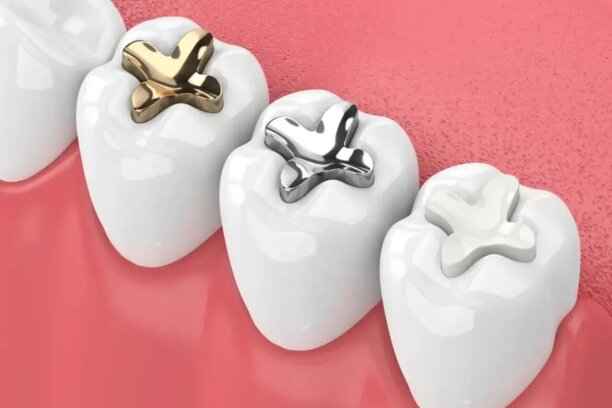

تتنوع أنواع حشوات الأسنان واسعارها لتناسب كل حالة حسب موقع السن، مدى التسوس، والهدف العلاجي بين المتانة والجمال. تشمل الحشوات الراتنجية، المعدنية، السيراميكية، الزجاج الشاردي، وحشو العصب، وتختلف الأسعار في السعودية حسب نوع المادة وتعقيد الحالة. يوفر مركز أضواء الحكمة ضمن عروض حشو اسنان خدمات عالية الجودة بأسعار مناسبة لجميع المرضى.

أنواع حشو الأسنان

تنقسم الحشوات إلى عدة أنواع، لكلٍ منها خصائصه ومجالات استخدامه، ويتم شرحها للمريض بشفافية كاملة قبل اتخاذ القرار النهائي.

1. حشو الزئبق (الفضي)

يُعد من أقدم أنواع الحشوات وأكثرها استخدامًا في الماضي، ولا يزال مناسبًا في بعض الحالات الوظيفية.

يمتاز هذا النوع بعدة خصائص:

- قوة تحمل عالية تجعله مناسبًا للأسنان الخلفية المعرضة لضغط المضغ الشديد.

- عمر افتراضي طويل مقارنة ببعض الأنواع الأخرى.

- مقاومة جيدة للتآكل مع مرور الزمن.

- تكلفة أقل نسبيًا، ما يجعله خيارًا اقتصاديًا في بعض الحالات.

- ثبات جيد داخل التجويف السني عند تركيبه بشكل صحيح.

2. حشو الحشوات المركبة (الراتنجية)

يُعد الخيار الأكثر شيوعًا حاليًا، خاصة لمن يبحثون عن التناسق الجمالي. ومن أبرز مميزاته:

- لون مطابق تقريبًا للون الأسنان الطبيعي.

- اندماج بصري ممتاز مع بنية السن.

- مناسب للأسنان الأمامية والخلفية على حد سواء.

- إمكانية تشكيله بدقة عالية لاستعادة الشكل الطبيعي.

- ارتباط قوي بمينا الأسنان عند تطبيقه بشكل صحيح.

3. حشو السيراميك

خيار متقدم يجمع بين الجمال والمتانة، ويُستخدم غالبًا في الحالات التي تتطلب مظهرًا راقيًا وعمرًا أطول. يمتاز حشو السيراميك بـ:

- مقاومة عالية للتصبغات وتغير اللون.

- مظهر قريب جدًا من الأسنان الطبيعية.

- تحمل جيد لقوى المضغ.

- سطح أملس يقلل من تراكم البلاك.

- ملاءمة ممتازة للحالات التجميلية المتقدمة.

4. حشو الذهب

رغم قلة استخدامه حاليًا، إلا أنه لا يزال خيارًا فعالًا في بعض الحالات الخاصة. من خصائصه:

- متانة استثنائية وعمر افتراضي طويل جدًا.

- توافق حيوي ممتاز مع أنسجة الفم.

- مقاومة عالية للتآكل والكسر.

- دقة عالية في التصنيع والتركيب.

- ثبات وظيفي ممتاز في الأسنان الخلفية.

أنواع مواد حشو الأسنان المختلفة

تتنوع مواد حشو الأسنان المختلفة لتناسب كل حالة:

- الحشوات الراتنجية المركبة: لون طبيعي ومرونة لتقليد مينا الأسنان، مناسبة للأمامية والخلفية.

- الحشوات المعدنية: مثل الزئبق أو الذهب، قوية وتتحمل الضغط، مثالية للأسنان الخلفية.

- الحشوات السيراميكية: مظهر جمالي ممتاز، مقاومة للتصبغات والتآكل، وتدوم طويلًا.

خصائص كل نوع من مواد حشو الأسنان

تختلف خصائص كل نوع من مواد حشو الأسنان بشكل كبير بحسب المادة المستخدمة، وموقع السن، والوظيفة المطلوبة، فاختيار الحشو الصحيح يضمن نتائج طويلة الأمد، ويمنع أي مضاعفات محتملة.

- الحشوات الراتنجية المركبة: لون طبيعي وتصاق جيد ومتانة مع مرونة.

- الحشوات المعدنية (الزئبق أو الذهب): متينة جداً وتتحمل الضغط، لكنها أقل جمالاً للأسنان الأمامية.

- الحشوات السيراميكية: صلبة وجمالية، مقاومة للتصبغ وسهلة التنظيف.